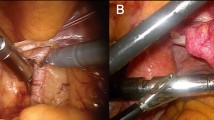

In patients with lymphoma the PET probe was used to locate a non-palpable lymph node during a diagnostic lymphadenectomy. The PET probe successfully located the target lymph nodes (neck, axilla and groin) in all cases. Figures 1, 2, 3 show a case of head and neck cancer where PET probe was used for diagnostic lymphadenectomy in the neck. In patients who underwent a metastasectomy procedure, surgical exploration was clearly facilitated by the use of the probe. It helped lead to the successful accomplishment of the surgical end-point (resection of the image-detected lesion). Probe-guided exploration was most rewarding in secondary explorations where the lesion(s) were obscured by the scar tissue. Manipulation of the probe in the surgical field was easy without any access difficulties. PET probe-guided surgery protocol is detailed in Table 2.